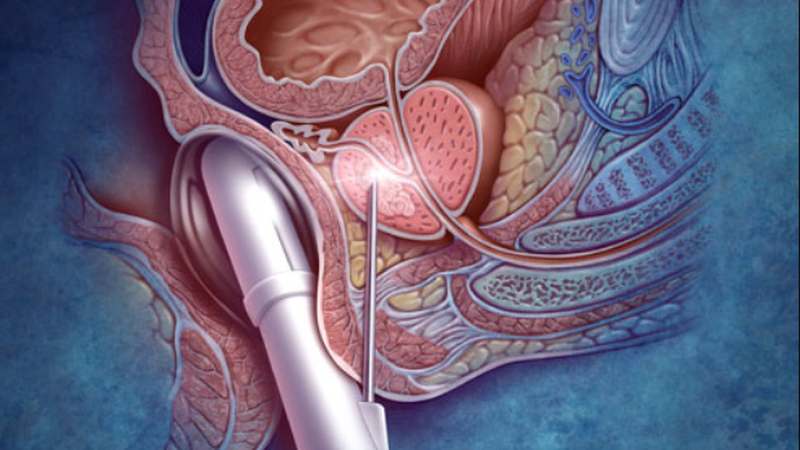

Siêu âm trực tràng, còn có tên gọi khác là siêu âm ngã trực tràng và siêu âm đầu dò trực tràng. Đây là phương pháp chẩn đoán hình ảnh rất được ưa chuộng nhờ có độ chính xác cao và hạn chế xâm lấn tối đa. Siêu âm qua ngã trực tràng được thực hiện bởi các bác sĩ giàu kinh nghiệm, đã được đào tạo bài bản và có nhiều năm thực hành.

Nguyên lý hoạt động của siêu âm đầu dò cũng giống như các hình thức siêu âm khác. Bác sĩ sẽ dùng một đầu dò chuyên dụng cùng với song siêu âm (sóng có tần số cao) đưa qua trực tràng để khảo sát các cơ quan trong vùng bụng dưới. Chẳng hạn như tử cung, buồng trứng, túi tinh,... Sau khi phát sóng siêu âm, hình ảnh thu nhỏ của các cơ quan này sẽ được hiển thị trên màn hình.

Quá trình thực hiện siêu âm bằng đầu dò thăm khám trực tràng thường sẽ bao gồm các bước sau:

Trong quá trình thực hiện, các bác sĩ sẽ tiến hành sinh thiết bệnh phẩm dưới hướng dẫn của phương pháp siêu âm trực tràng nếu thấy có dấu hiệu nghi ngờ ung thư trực tràng. Mẫu sinh thiết sẽ được đặt trong lọ chứa chuyên dụng và đánh số vị trí, sau đó chuyển sang khoa giải phẫu để tiến hành kiểm tra và đánh giá.